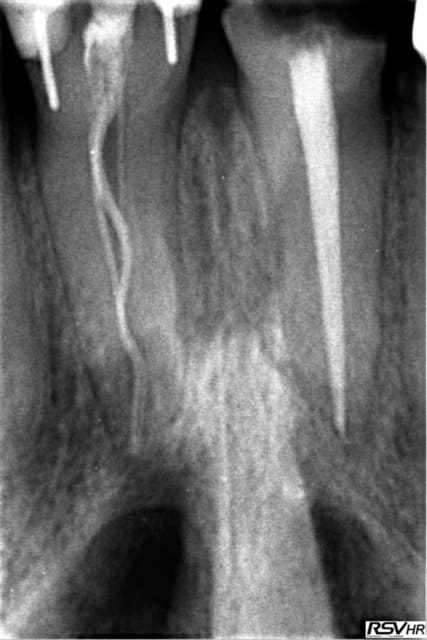

Made in Portugal pour la première

Made in France pour la seconde